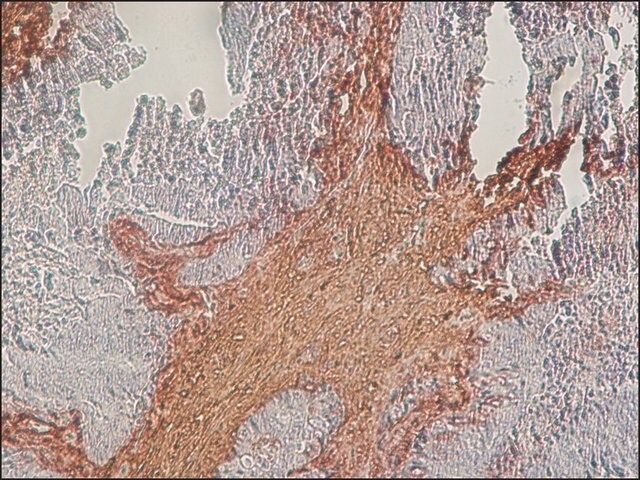

| technique(s) | immunofluorescence: 2.5-5 μg/mL using bovine BMGE cells immunohistochemistry: 2.5-5 μg/mL using heat-retrieved formalin-fixed, paraffin-embedded human colon cancer sections and Biotin/ExtrAvidin ®-Peroxidase staining system. |